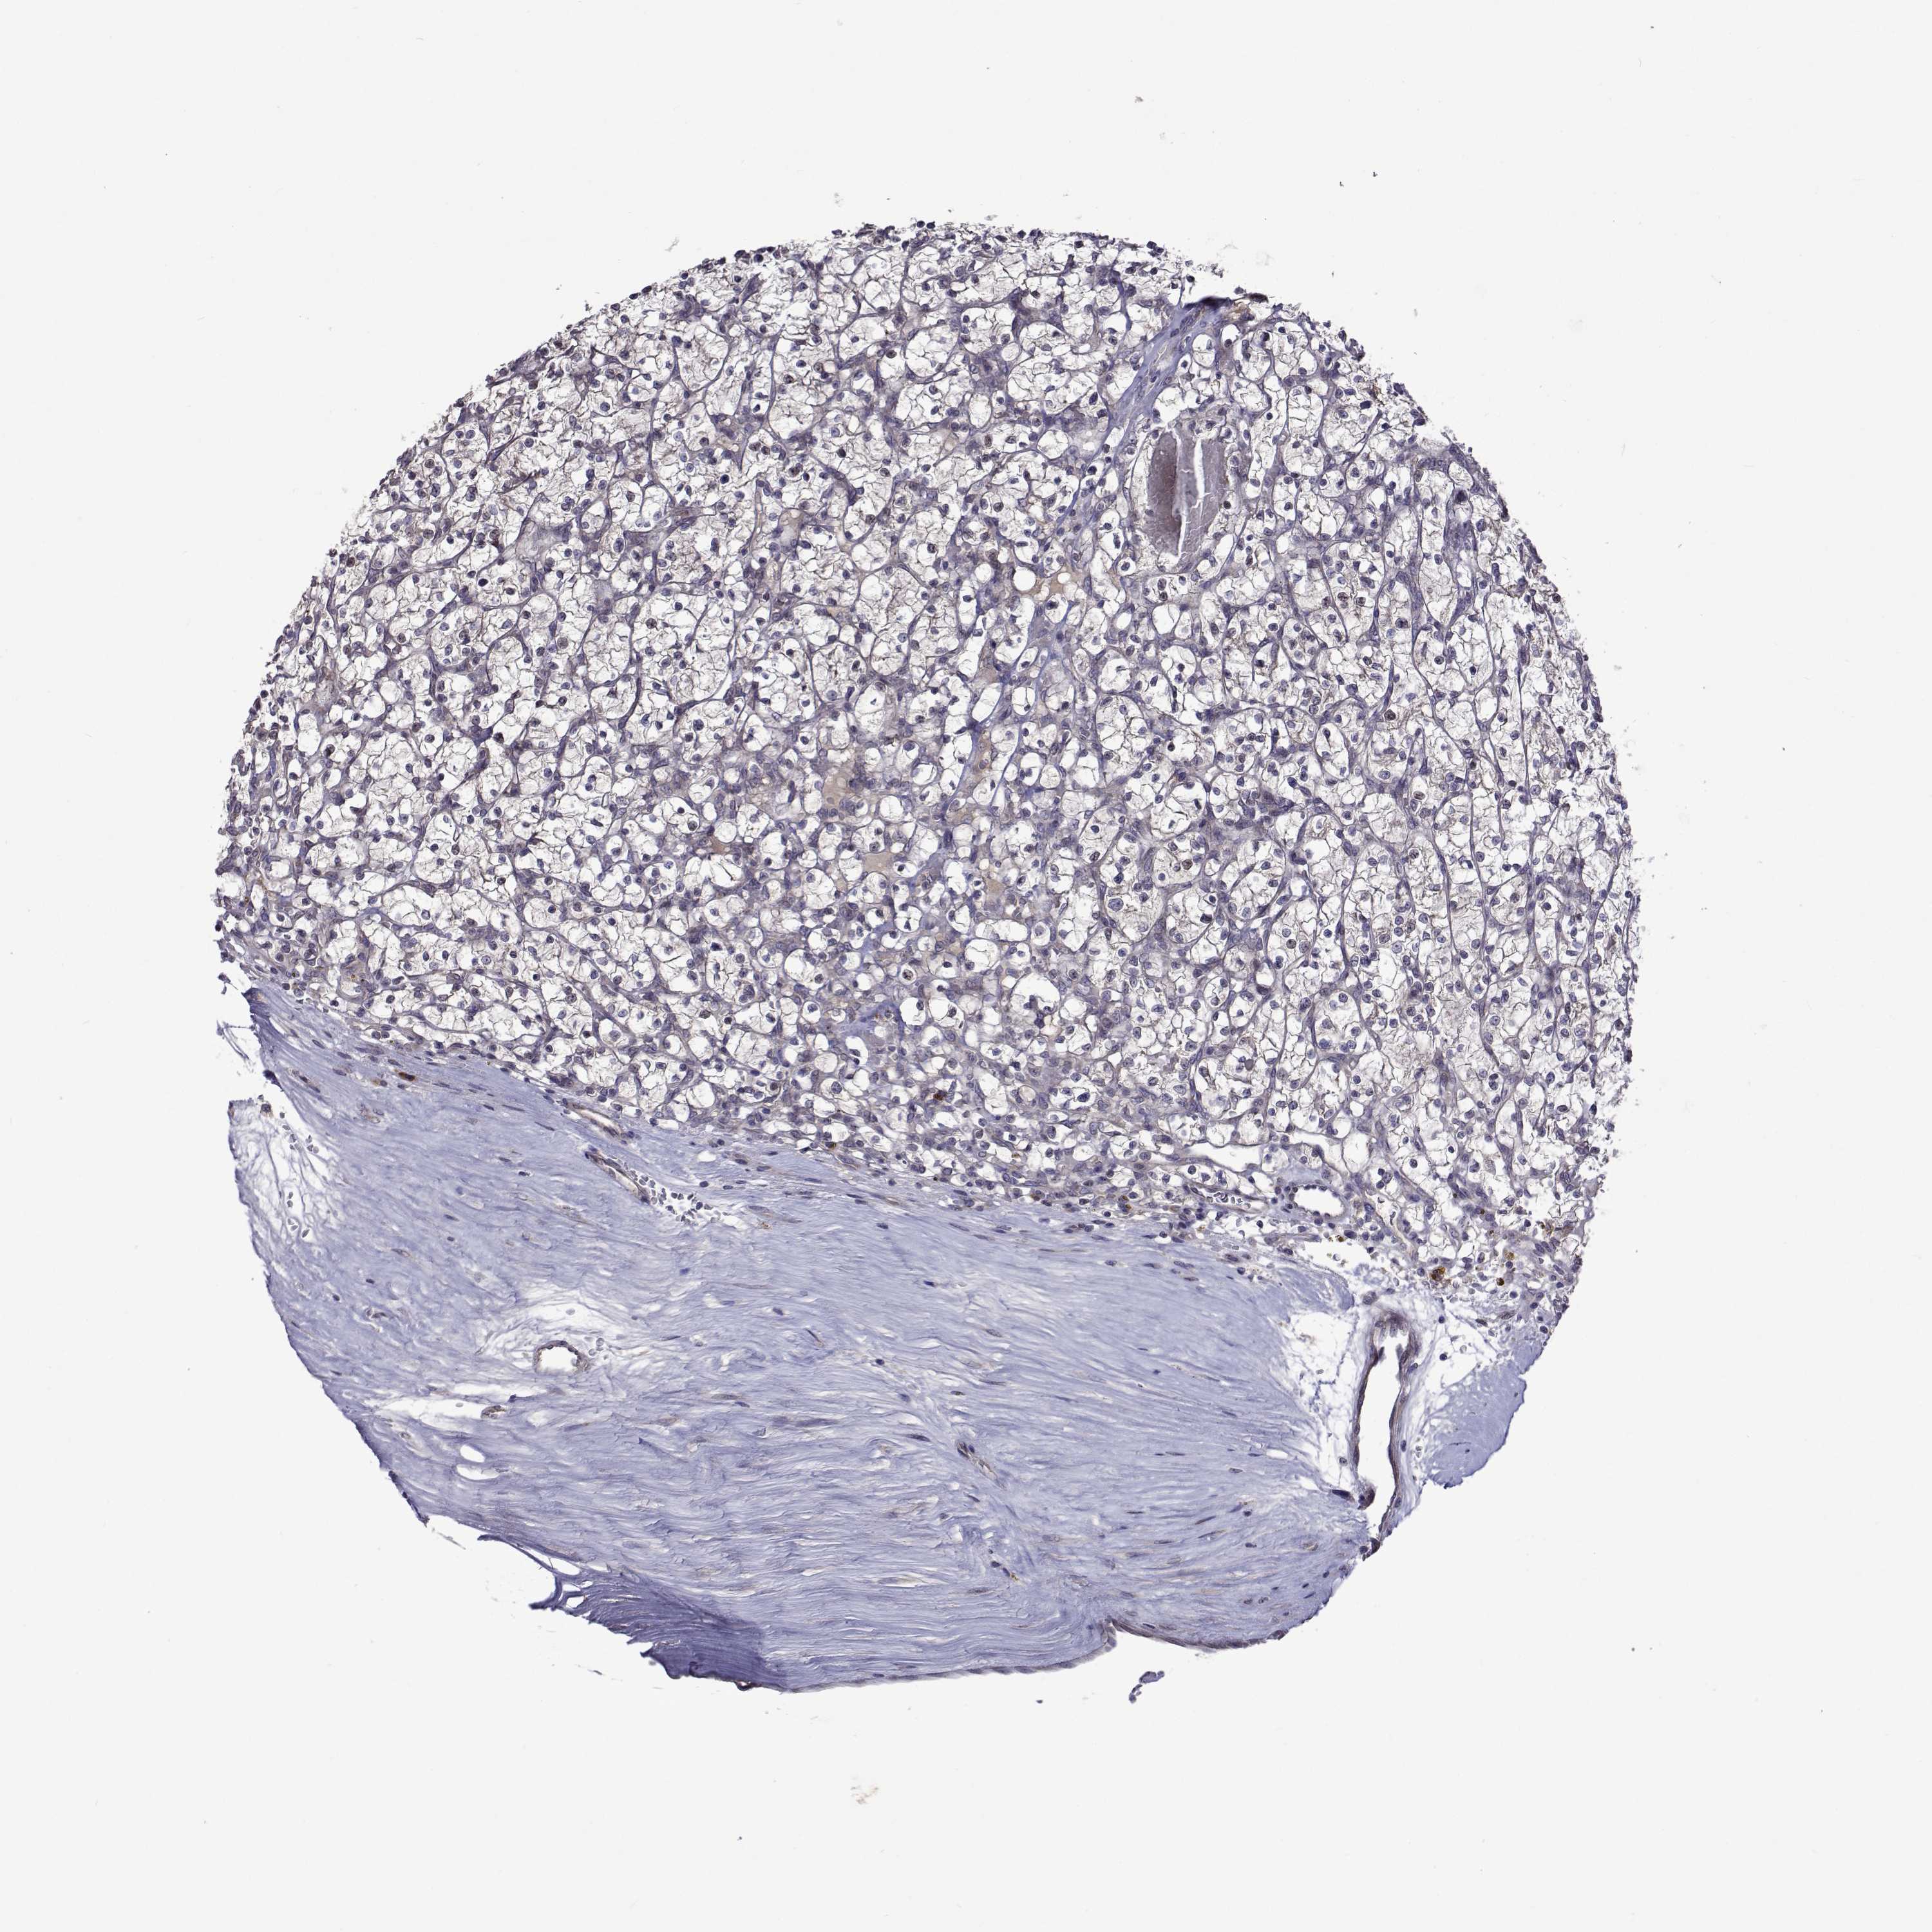

KIDNEY RENAL CLEAR CELL CARCINOMA (VALIDATION) - Interactive survival scatter ploti

The Survival Scatter plot shows the clinical status (i.e. dead or alive) for all individuals in the patient cohort, based on the same data that underlies the corresponding Kaplan-Meier plots. Patients that are alive at last time for follow-up are shown in blue and patients who have died during the study are shown in red.

The x-axis shows the expression levels (FPKM) of the investigated gene in the tumor tissue at the time of diagnosis. The y-axis shows the follow-up time after diagnosis (years). Both axes are complimented with kernel density curves demonstrating the data density over the axes. The top density plot shows the expression levels (FPKM) distribution among dead (red) and alive patients (blue). The right density plot shows the data density of the survived years of dead patients with high and low expression levels respectively, stratified using the cutoff indicated by the vertical dashed line through the Survival Scatter plot. This cutoff is automatically defined based on the FPKM cutoff that minimizes the p-score. The cutoff can be changed by dragging the vertical line or by entering a cutoff value in the square labeled "Current cut-off".

Under the Survival Scatter plot the p-score landscape (black curve; left axis) is shown together with dead median separation (red curve; right axis). Dead median separation is the difference in median mRNA expression between patients who have died with high and low expression, respectively. It is calculated as follows: median FPKM expression of dead patients with high expression - median FPKM expression of dead patients with low expression. This is intended to aid the user in visually exploring custom cutoffs and the associated p-scores and dead median separation.

Individual patient data is displayed and can be filtered by clicking on one or more of the category buttons on the top of the page. Categories describing expression level and patient information include: high, low, alive, dead, female, male and tumor stages. The scale of the x-axis can be toggled between linear and log-scale by clicking on the "x log" button. Mouse-over function shows TCGA ID, patient information and mRNA expression (FPKM) for each patient.

& Survival analysisi

Kaplan-Meier plots summarize results from analysis of correlation between mRNA expression level and patient survival. Patients were divided based on level of expression into one of the two groups "low" (under cut off) or "high" (over cut off). X-axis shows time for survival (years) and y-axis shows the probability of survival, where 1.0 corresponds to 100 percent.

TARBP2 is validated prognostic, high expression is unfavorable in Kidney Renal Clear Cell Carcinoma (validation)

Best expression cut offi

Based on the FPKM value of each gene, patients were classified into two groups and association between prognosis (survival) and gene expression (FPKM) was examined. The best expression cut-off refers the FPKM value that yields maximal difference with regard to survival between the two groups at the lowest log-rank P-value. Best expression cut-off was selected based on survival analysis .

When clicking on this number, the vertical dashed line indicating cut-off, the interactive survival plot, and the Kaplan-Meier curve will be adjusted to show results based on the best expression cut-off.

: 11.85

TCGA RNA samplesi

RNA-seq data is reported as average FPKM (number Fragments Per Kilobase of exon per Million reads), generated by the The Cancer Genome Atlas (TCGA) .

Normal distribution across the dataset is visualized with box plots, shown as median and 25th and 75th percentiles. Points are displayed as outliers if they are above or below 1.5 times the interquartile range. FPKM values of the individual samples are presented next to the box plot.

Average pTPM 13.3

Number of samples 100